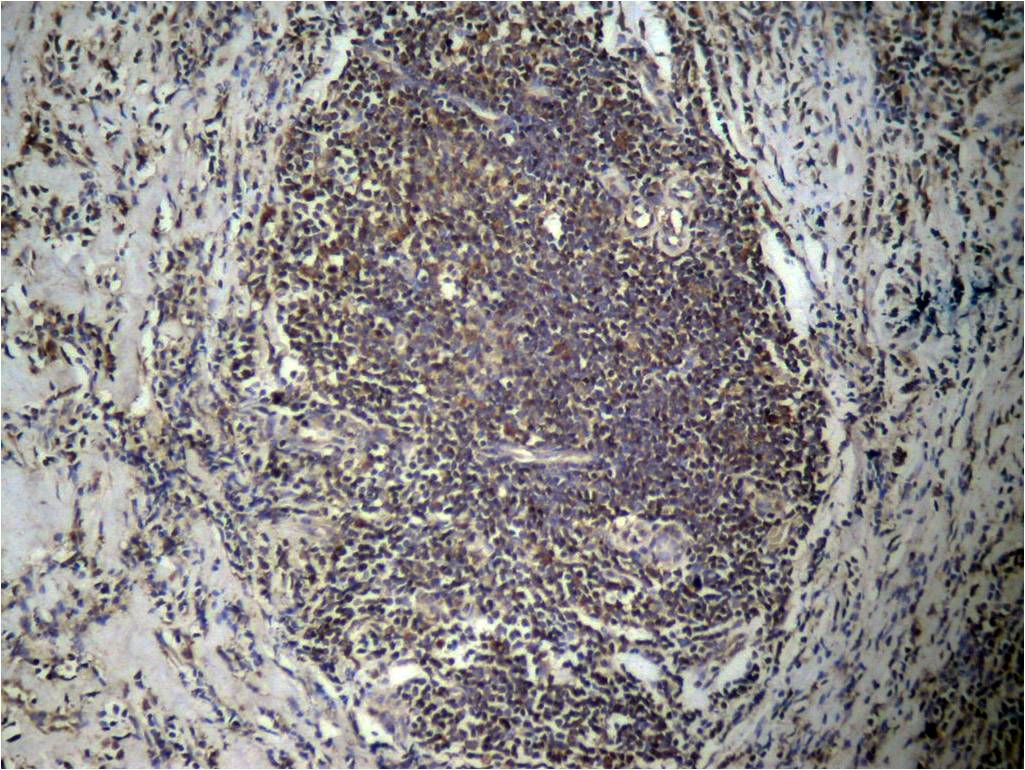

Immunohistochemical analysis of paraffin-embedded human breast carcinoma tissue using Histone H3 (Di-Methyl-Lys27) Antibody #11583.